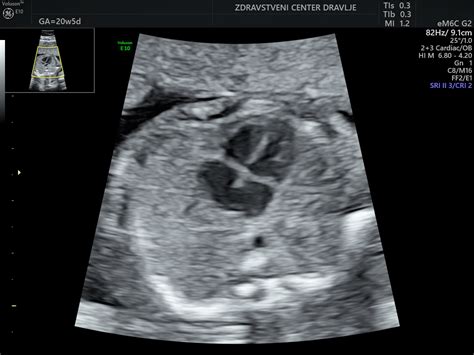

Položaj ploda se lahko v tem tednu še vedno spreminja. Večina plodov se proti koncu drugega trimesečja začne ustaljevati v določenem položaju. Če plod leži s hrbtom naprej, se njegovi sprednji deli morda slabše vidijo na ultrazvoku, kar je pomembno pri morfologiji ploda. Vendar pa se lega ploda lahko še dolgo časa spreminja, kot mu ustreza. Zato lahko občutek brce ali pritiska variira glede na lego otroka. Nekatere nosečnice v tem obdobju že čutijo nežne gibe ploda, še posebej, če je posteljica na zadnji steni ali če je nosečnica že rodila.